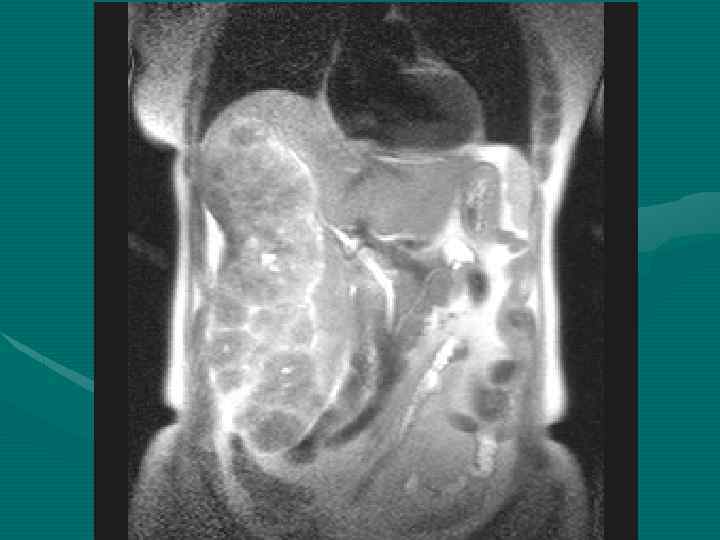

Методы диагностики опухолевой патологии печени. • • • УЗКТ Обследование по органам КТ с контрастированием МРТ с контрастированием Ангиография Пункционная биопсия Опухолевые маркеры (СА-19 -9, РЭА, АФП) Лапароскопия ПЭТ Лапаротомия с удалением опухолевого очага Динамическое наблюдение

Диагностические задачи 1. Являются ли выявленные изменения опухолью? 2. Какова природа опухоли: доброкачественная или злокачественная? 3. Точное указание пораженной доли печени. 4. Точное указание пораженного сегмента печени. 5. Имеется ли поражение ворот печени? 6. Инвазия в окружающие печень структуры. 7. Имеются ли внепеченочные метастазы?